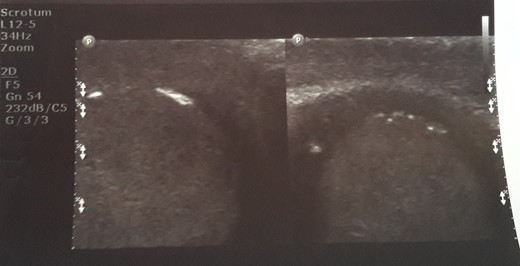

Initial sonographic findings were suggestive of epididymo-orchitis. The testis was well perfused and in normal position (Fig. 1). He was admitted for 3 days to start intravenous anti-inflammatory and antibiotic treatment and discharged under antibiotic treatment. Re-examinations were scheduled to assess treatment. On first reexamination, a week later, edema had subsided and the testis appeared hard, indurated and painless (Fig. 2). Ultrasound was still suggestive of epididymo-orchitis. Nevertheless suspicion for a testicular tumor was raised because of persistence of clinical and sonographic findings. An earlier appointment was scheduled this time. Five days later, at the second reexamination, another ultrasound showed reduced testicular perfusion that reached only the periphery of the testicular parenchyma (Fig. 3). The boy was operated as an emergency. Intraoperatively testis was non-twisted, with normal vas and vessels that ended in a necrotic testicular parenchyma. The testis was dark brown, hard on palpation and no blood came out when incised (Fig. 4). Right orchidectomy was performed. Since the exact cause of testicular necrosis was still unkown at the time of operation a left orchidopexy was performed to protect the only surviving testis from any future risk of torsion. The boy was discharged the next day. Histology showed a case of epididymitis nodosa and ruptured sperm granuloma that caused vascular compression, thrombosis and testicular necrosis (Fig. 5). More specifically, it showed proliferation of small ducts and gland-like structures in the walls of the vas deferens and epididymis in response to fluid and sperm dissection into the interstitium secondary to mechanical obstruction and increased intraluminal pressure. These findings are extremely rare in pediatric patients. The boy had an uneventful postoperative course and was discharged 2 days after surgery able to travel by sea to his home island.

Five days later another ultrasound showed reduced testicular perfusion that reached only the periphery of the testicular parenchyma.